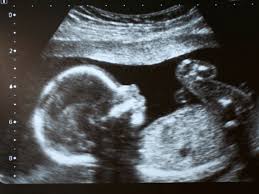

¿Os habéis preguntado alguna vez desde cuándo empiezan a oír los bebés en la etapa prenatal?

El aparato auditivo se termina de desarrollar alrededor del tercer mes y medio. El bebé en gestación empezará a escuchar entre el 4º y el 5º mes. A partir de ahí puede recibir estimulación sensorial del exterior, y ésta es muy importante para su desarrollo.

Aún así, hay que tener en cuenta que los sonidos dentro del útero son diferentes a como los oímos nosotros en el exterior. El ambiente sonoro del feto es muy ruidoso, ya que se encuentra inmerso en todos los sonidos que producen la circulación, el aparato digestivo, el corazón y los pulmones de la madre. Y los sonidos del exterior son amortiguados por todas las estructuras que deben atravesar: la pared abdominal de la madre, la bolsa y el líquido amniótico.

El feto es estimulado por los sonidos que percibe su oído y por las vibraciones que recibe a través del líquido amniótico.